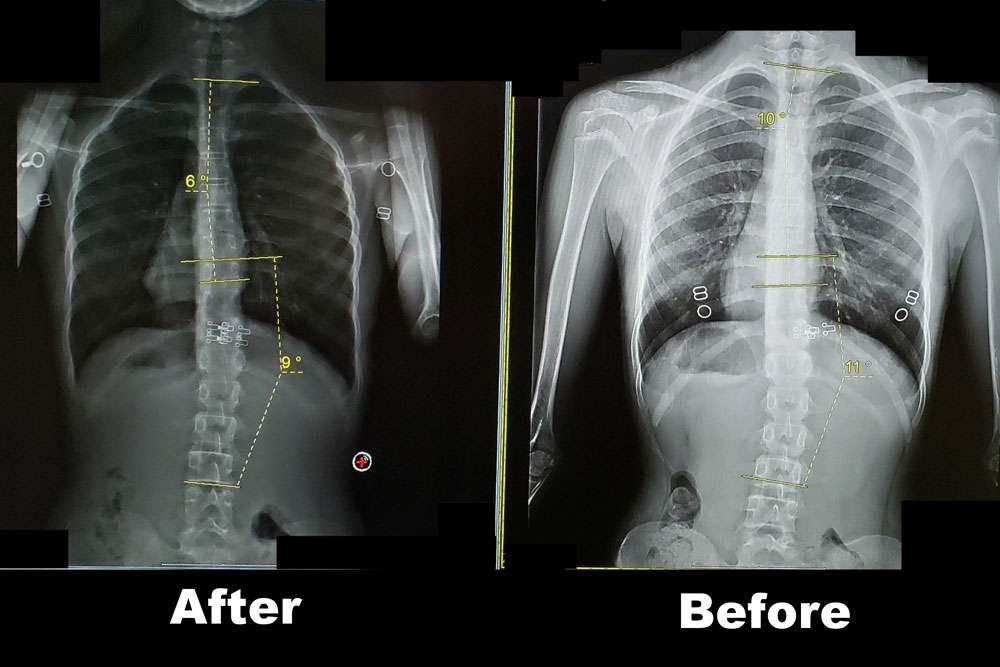

This patient is a 13-year-old female with an original curve measuring 22 degrees. In this comparison, the before x-ray was after she had been doing Schroth training for 2 months. (We did not have access to the original x-ray) The after x-ray was 6 months following. She showed a significant reduction in her curve to 6 degrees in the thoracic and 9 degrees in the lumbar. (under 10 degrees is not considered scoliosis!) This is a great example of a mild curve reducing with scoliosis specific exercise.